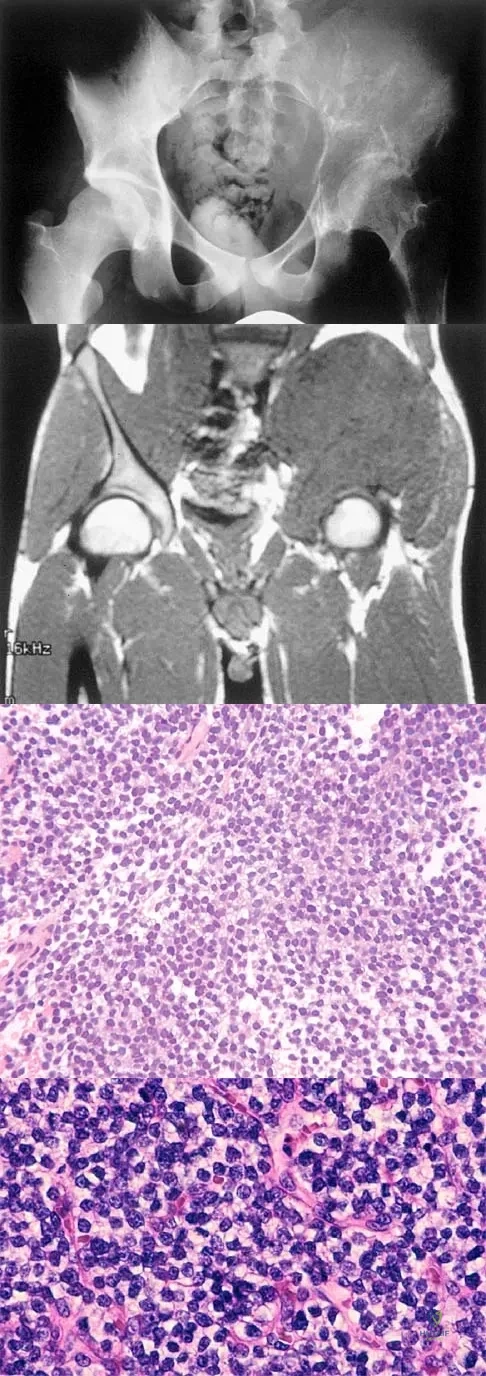

A 25-year-old man has had an insidious onset of left hip pain over the past 11 months. A radiograph, coronal MRI scan, and histopathologic specimens are seen in Figures 2a through 2d. What is the most likely diagnosis?

Explanation